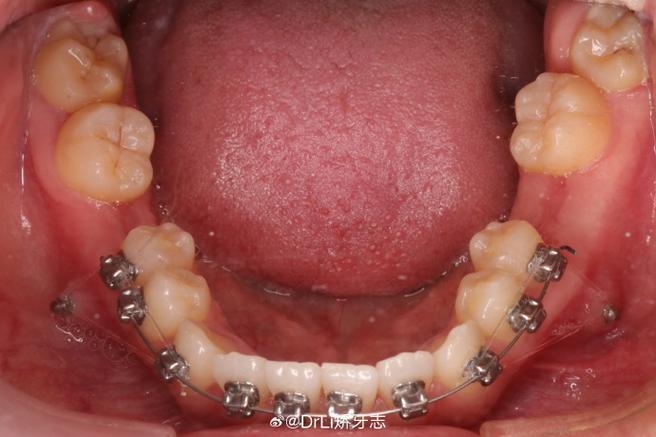

| 结扎固定 | ①不锈钢丝结扎:用结扎钳将0.008-0.010英寸不锈钢丝“8”字形缠绕托槽翼与弓丝,末端剪断后弯向牙面;②弹性圈结扎:选用合适直径的弹性圈(如灰色、蓝色)套住托槽翼与弓丝,确保无扭转。 | 结扎钳、不锈钢结扎丝、弹性结扎圈 | 不锈钢丝结扎需力度均匀,避免单侧过紧;弹性圈需定期更换(2-4周),因弹性会随时间衰减。 |